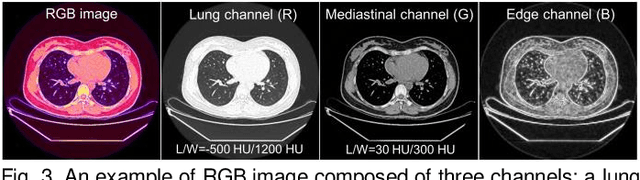

Abstract:Existing Masked Image Modeling (MIM) depends on a spatial patch-based masking-reconstruction strategy to perceive objects'features from unlabeled images, which may face two limitations when applied to chest CT: 1) inefficient feature learning due to complex anatomical details presented in CT images, and 2) suboptimal knowledge transfer owing to input disparity between upstream and downstream models. To address these issues, we propose a new MIM method named Tissue-Contrastive Semi-Masked Autoencoder (TCS-MAE) for modeling chest CT images. Our method has two novel designs: 1) a tissue-based masking-reconstruction strategy to capture more fine-grained anatomical features, and 2) a dual-AE architecture with contrastive learning between the masked and original image views to bridge the gap of the upstream and downstream models. To validate our method, we systematically investigate representative contrastive, generative, and hybrid self-supervised learning methods on top of tasks involving segmenting pneumonia, mediastinal tumors, and various organs. The results demonstrate that, compared to existing methods, our TCS-MAE more effectively learns tissue-aware representations, thereby significantly enhancing segmentation performance across all tasks.